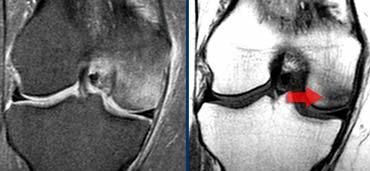

Viêm xương sụn bóc tách

Chẩn đoán Viêm xương sụn bóc tách thường được thực hiện trên X-quang.

Câu hỏi đặt ra khi chụp MRI là tổn thương ổn định hay không ổn định.

Ca lâm sàng bên trái là không ổn định vì hai lý do:

– Các nang nhỏ ở nền tổn thương (mũi tên đỏ)

– Quan trọng hơn là có dịch ở nền tổn thương (mũi tên xanh)

Lưu ý rằng lớp dịch này khác với AVN, nơi dịch nằm giữa sụn và xương.

Viêm xương sụn bóc tách không ổn định. Dấu hiệu duy nhất có giá trị để chẩn đoán OD không ổn định là dịch (mũi tên vàng), không phải phù tủy hay gián đoạn bề mặt xương sụn (mũi tên xanh lá).

Các dấu hiệu không có giá trị trong việc phân biệt OD ổn định và không ổn định bao gồm:

– Phù tủy xương (có thể gặp trong cả hai trường hợp)

– Gián đoạn bề mặt xương sụn.

Vì vậy, ca lâm sàng bên trái là không ổn định vì có dịch ở nền tổn thương.

Ca lâm sàng bên trái cho thấy viêm xương sụn bóc tách với phù tủy xương và gián đoạn bề mặt xương sụn.

Tuy nhiên, vì không có dịch, chúng ta không thể xác định đây là tổn thương ổn định hay không ổn định.

Trong phẫu thuật, tổn thương viêm xương sụn bóc tách được xác nhận là ổn định.

Trong những trường hợp không thể xác định tổn thương ổn định hay không ổn định, chụp MRI khớp có thuốc tương phản từ (MR-arthrogram) rất có giá trị.

Chúng ta tìm kiếm dấu hiệu Gadolinium thấm vào xung quanh tổn thương xương sụn.